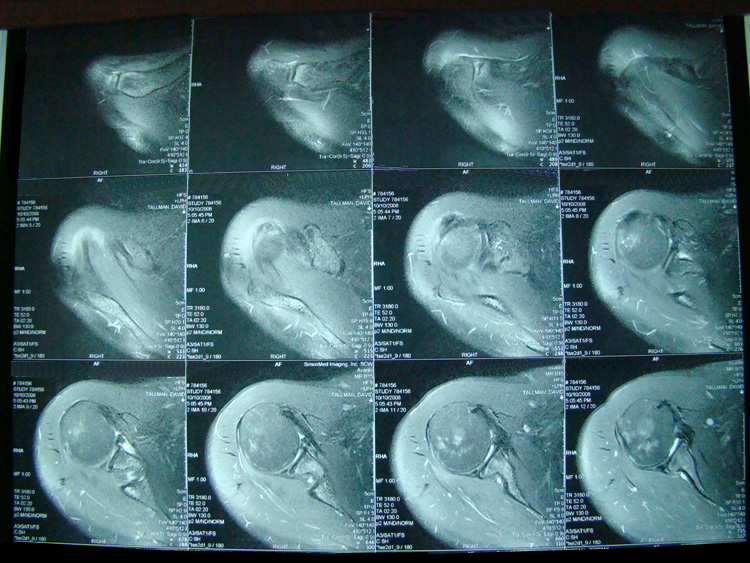

March 2019 MRI

IMPRESSION:

- Complete rupture proximal third anterior cruciate ligament with pivot shift

pattern of bone injuries lateral compartment and contrecoup bone contusion

medial tibial plateau. Joint hemarthrosis. - Complex tear lateral meniscus with inferiorly flipped flap tear extending

into the popliteal hiatus. - Complex tear medial meniscus with outwardly extruded tears of the posterior

horn and body. - Low-grade sprains medial collateral ligament and medial posterior oblique

ligament. - Low-grade sprains fibular collateral ligament and anterolateral ligament.

Intermediate to high-grade sprain popliteofibular ligament and arcuate ligament. - Grade 1 strains vastus lateralis, short head biceps, sartorius, soleus,

popliteus and anterior compartment muscles.

May 2019 MRI

IMPRESSION

- Near full-thickness tear of the anterior cruciate ligament femoral attachment with

associated edema in the intercondylar notch. This is best seen on axial and coronal

images. - Pivot shift bone contusions in a pattern typical of this injury.

- Medial meniscus: Complex tear of the posterior horn of the peripheral third

compromising superior and inferior articular surfaces, with the tear more horizontal

towards the posterior horn/body junction.

December 2019 MRI

- Medial: Nondisplaced horizontal longitudinal tear extending obliquely to the

undersurface of the meniscal body and posterior horn segments. No chondral erosion or thinning. Intact root ligaments. - Intact anterior cruciate ligament. Normal posterior cruciate ligament. Intact medial

lateral supporting structures. - No joint effusion or synovitis. No periarticular muscle injury. No osseous contusion

or stress injury. Minimal fluid in the semimembranosus-medial gastrocnemius bursa. No

frank Baker's cyst.

June 2020 MRI

- Healed femoral-sided ACL tear with partial attenuation of the proximal ACL fibers.

- Progressive healing of horizontal oblique tear of the medial meniscus posterior horn.

- Chronic inferiorly displaced meniscal flap tear at the lateral meniscus posterior

horn-root junction, less conspicuous than on prior MR imaging. Resolution of previously

noted horizontal longitudinal tear of the body-posterior horn segments. - No new evidence of internal derangement. No acute osseous abnormality.